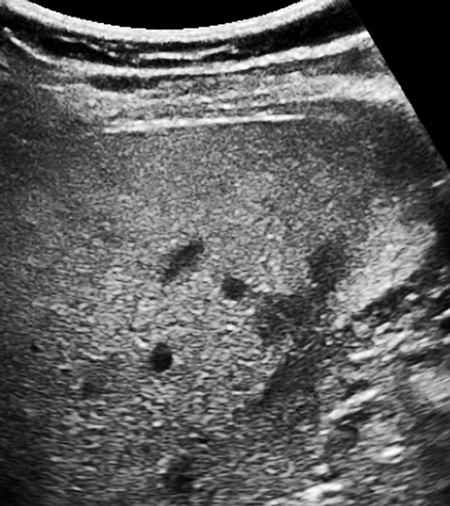

Normal ultrasound liver pattern. Echogenicity and echodensity of the …

ultrasound scan showing increased echotexture of the liver in …